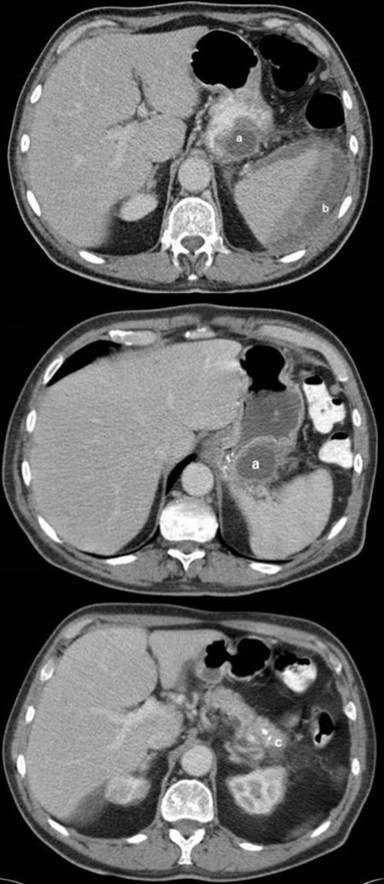

A contrast CT-scan of his abdomen (Figure 1) showed a large pseudocyst at the tail of the pancreas (37x33 mm) and a large, spontaneous, contained, subsplenic haemorrhage (96x55 mm). Furthermore, some minor calcification in the body of the pancreas was noted. The gallbladder and biliary tree were normal. The patient was initially kept nil by mouth for 48 hours and given supplementary i.v. fluids, analgesia and antiemetics for his acute pancreatitis.

Figure 1. Initial CT scan on admission showing a large pseudocyst (a.) measuring (37x33 mm) within the pancreatic tail, associated subcapsular splenic haemorrhage (b.) measuring (96x55 mm) and calcification in the pancreatic body (c.) |